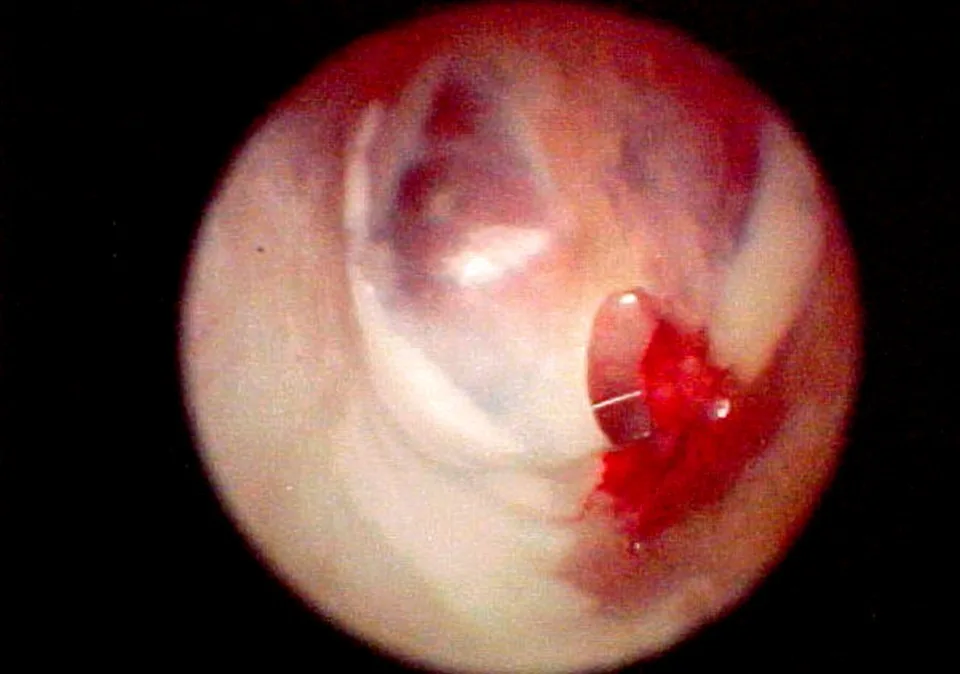

Regardless of whether the incision is made with a video or surgical otoscope, any bleeding indicates that it was not made in the proper position. Damage to either the pars flaccida or the malleus bone results in bleeding, which can slow healing.